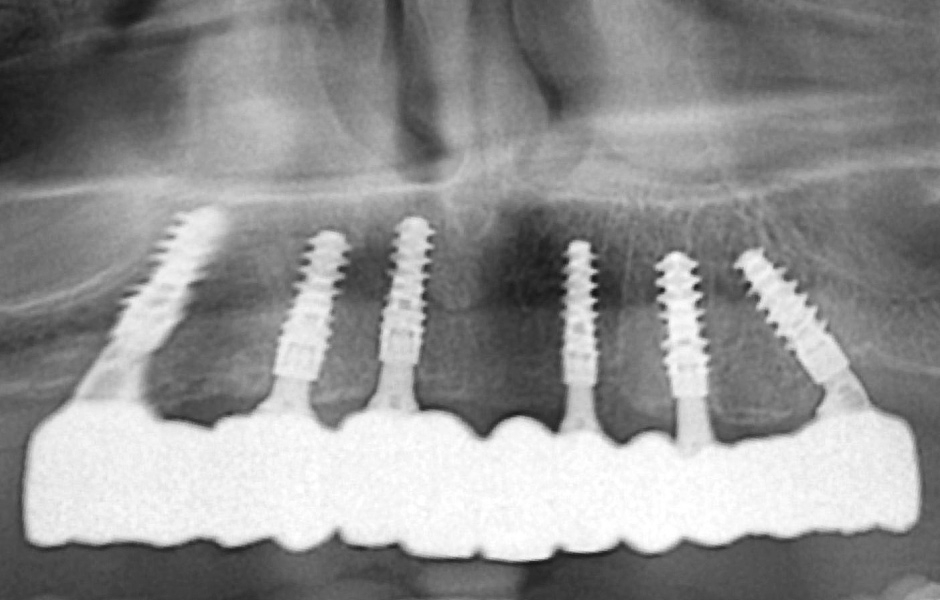

Kontrolní rentgenový snímek potvrdil, že jsou všechny klinické parametry v normě (obr. 43).

Definitivní náhrada byla nasazena a ověřena z hlediska estetiky, okluze a funkce (obr. 51–55). Panoramatický kontrolní snímek potvrdil, že všechny parametry protetického ošetření odpovídají očekávaným hodnotám (obr. 56).

Obr. 56